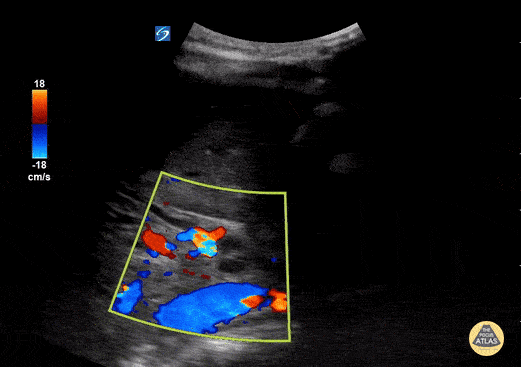

Peds-Biliary - Dilated Common Bile Duct - Color Doppler (2/3)

11 year old female with abd pain and emesis. Kicked in stomach by horse 6 weeks prior with grade 4 liver lac. Seen a few days ago with reassuring labs and US. Now with rising aminases and bilirubin. POCUS demonstrated a dilated and edematous gallbladder with sludge, and a dilated CBD and the classic 'double barrel' sign. Contributed by: Matthew Moake, MD PhD